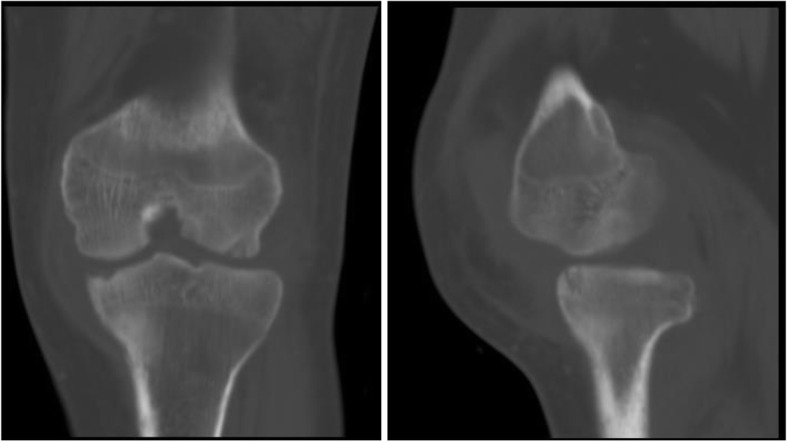

Fig. 2.

CT (anteroposterior and lateral): severe joint destruction and central and peripheral erosions